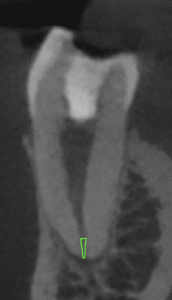

拡大すると、

この根尖部の緑色の部分のせめぎ合いだろう。

ここが既に#40.04になっているということで術後疼痛が出ているということであれば、できることはさらなる拡大だ。